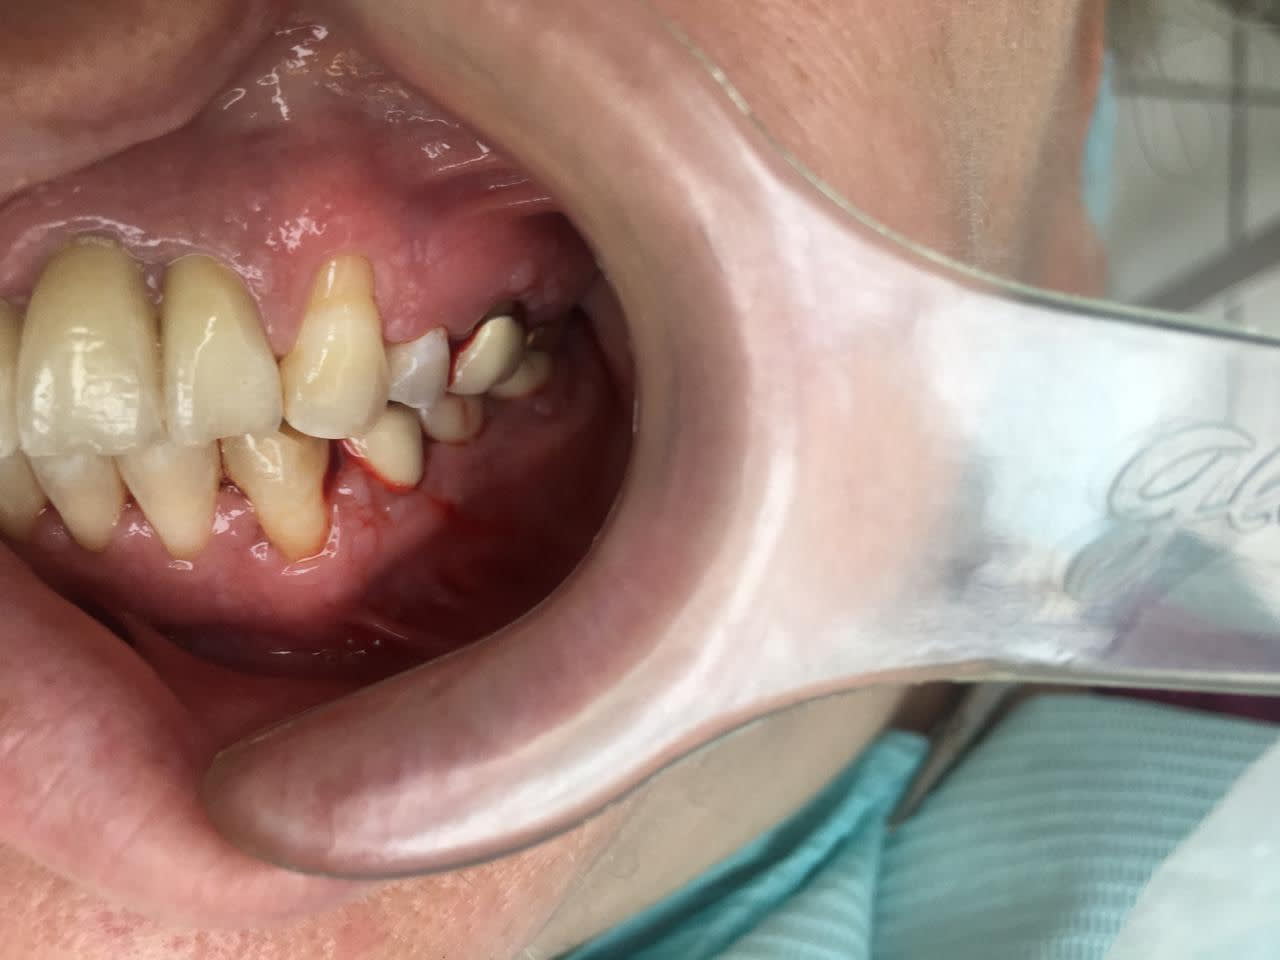

J'ai reçu au cabinet pour un check up annuel une patiente âgée de 37 ans, sans antécédent particulier et pas de traitement en cours. elle presente au niveau de la gencive et des joues internes de multiples petites vesicules, indolores au toucher.

Je ne les vois pas sur la photographie.

Par contre, la décapitation des papilles des incisives latérales est frappant!

Belle parodontite à priori autour de coiffes mais pas que...

Les vésicules dans les joues sont probablement des grains de Fordyce.